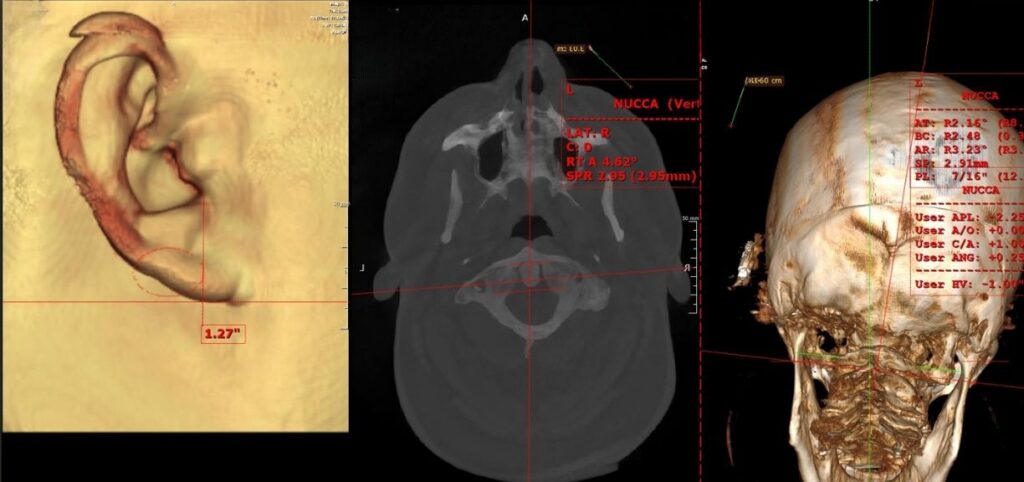

Advanced Imaging Enhancing Chiropractic Care

I went in to see Dr. Norris after having bad migraines and having my arms fall asleep on a regular basis. Dr. Norris was very knowledgeable and explained all of the reasons why I was in this pain and how he can help. He then did 3 separate scans and an X-ray to get a clear treatment plan. I’m very excited to know I will not only be able to feel my progress but we will be able to track it with these scans. We finished with an adjustment that instantly relieved my neck pain and migraine. He popped my rib back in and helped my shoulder. I’m going back Monday to go over the treatment plan. I’m so grateful to finally find someone that can not only help me feel better but also actually fix my back.

Dr. Norris was very kind as well, i was able to book an appt on Friday post procedure. He talked me through NUCCA (as my current local provider uses a slightly different technique), explaining how it worked, the history, and differences between that and my current technique.